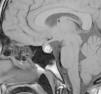

The patient was referred to the paediatric endocrinology unit after testing revealed an elevated prolactin level (198ng/mL; normal value range, 8.5–26.5ng/mL). During the structured interview, the patient reported one year of intermittent blurry vision and frontal headache of three months’ duration accompanied by light unilateral galactorrhoea. The findings of the physical examination were: height, 169.5cm (standard deviation [SD], +1.1); weight, 53.3kg; body mass index (BMI), 19.29kg/m2 (SD, −0.79). The patient was at Tanner stage V of pubertal development with proportionate features. There was no galactorrhoea, hirsutism or acne. The complete blood count and blood chemistry panel were normal, with the most salient finding being the serum prolactin level (205.6ng/mL). Magnetic resonance imaging (MRI) revealed an enlarged pituitary gland with a superior border that was convex towards the midline and signal hyperintensity suggestive of subacute haemorrhage (Fig. 1). The pituitary gland extended into and obliterated the suprasellar cistern, exerting a mass effect on the optic chiasm. The ophthalmological examination evinced mild hyperopia, and the visual field test and eye fundus examination were normal. The patient was given a diagnosis of prolactinoma with subclinical apoplexy based on these findings, and started treatment with cabergoline at a dose of 0.25mg the first week, followed by a maintenance dose of 0.50mg a week. One month after treatment initiation, the follow-up MRI scan showed an adenoma measuring 10mm×8mm (Fig. 2), values that may have been overestimated due to haemorrhagic features, and the serum prolactin level was 12.6ng/mL. At present, the patient has regular menstrual periods, normal vision without headache and no galactorrhoea.